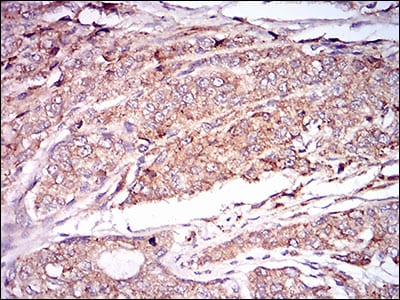

Immunohistochemical analysis of paraffin-embedded human prostate cancer tissues using CAMK2G mouse mAb with DAB staining.